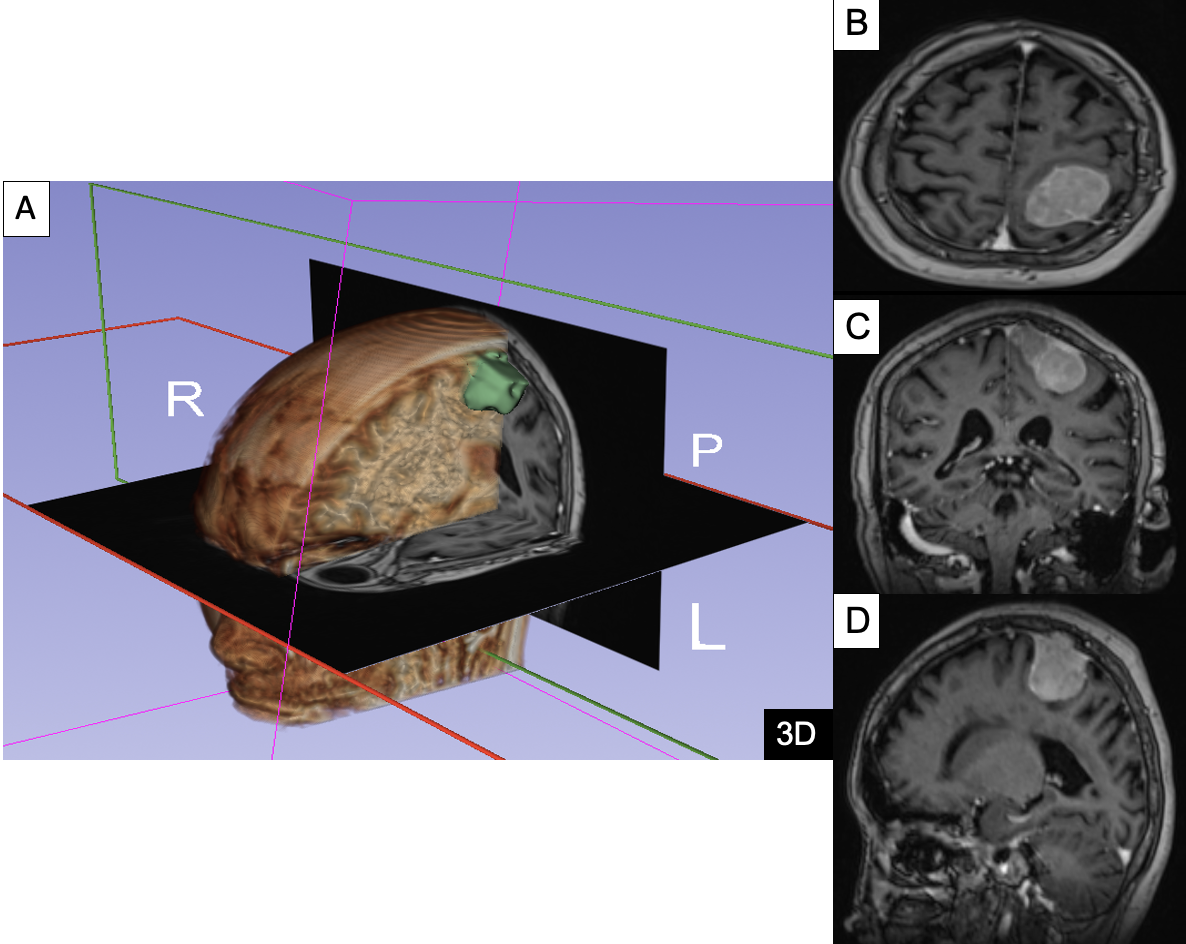

Hình 1. Hình ảnh khối thoát vị vùng cột sống thắt lưng cùng, hình vòm, bờ rõ, 5x7cm, phần da bao phủ còn nguyên vẹn (A), bàn chân khoèo (B), hình ảnh giãn não thất trên MRI chuỗi xung T1 Gado ở mặt phẳng cắt ngang (C), đứng dọc (D), đứng ngang (E)